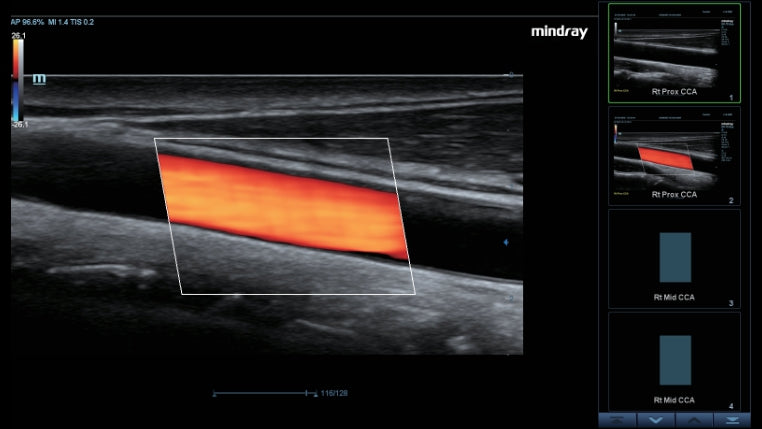

Como una solución de obstetricia, ginecología e imagen general completa, proporciona una interfaz muy robusta e intuitiva. Supera las expectativas de tus rastreos con su sistema de transductores pure crystal

| Marca: | Mindray | Modelo: | DC-40 FullHD | Altura: | 1.2 m - 1.65 m | Anchura: | 543 | ||||